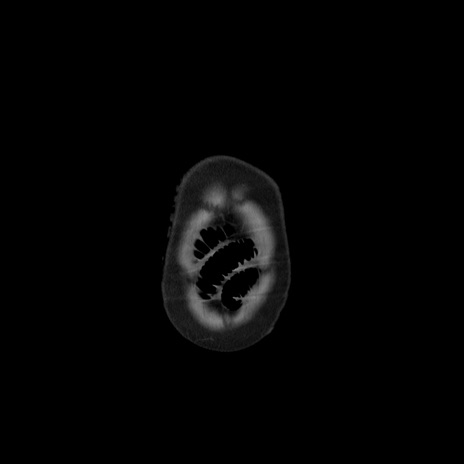

矢状断像